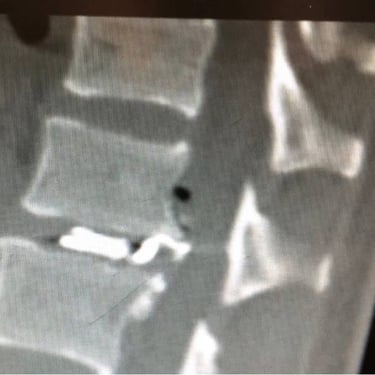

An intriguing case involved severe herniation and disc rupture between L4 and L5 vertebrae, causing intense pain. Opting out of surgery, the patient chose to try Discogel. Due to severe foraminal stenosis from the extruded disc, the Discogel injection was cautiously prolonged to one hour. Post-injection CT scan revealed effective penetration into fragmented disc components in the narrowed foraminal space.

The patient's pain gradually diminished after 4-5 weeks, and complete relief was achieved after several months.

The first image is six months post-injection, and the second image is three years post-injection."

Important Note: Foraminal disc herniation and migration into the intervertebral foramen significantly reduce the likelihood of a favorable response to Discogel injection and are not recommended for such cases.